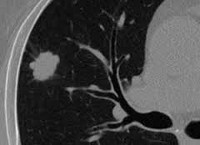

Рентгенологическая картина зависит от формы (узловой, полостной, верхушечной, пневмониеподобной) периферического рака легкого. Наиболее типично выявление неоднородной тени шаровидной формы с неровными контурами в окружении нежного «лучистого венчика»; иногда определяются полости распада. При раке Панкоста нередко обнаруживается деструкция I-III ребер, нижних шейных и верхних грудных позвонков. На бронхограммах видны ампутации мелких бронхов, сужение бронхиальных ветвей. В сложных случаях используется рентгеновская КТ или МРТ легких.